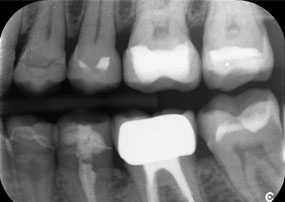

Provocarea consta în îndepărtarea a douăsprezece coroane fixate cu aliaj metalic, fără a deteriora dinții de susținere. Piesa de mână a fost utilizată pentru secționarea foarte precisă a straturilor ceramice și divizarea structurii metalice cu ajutorul unei freze din carbură, permițând astfel îndepărtarea coroanei cu un grad minim de traumatizare. În doar 30 de minute, vechile restaurări au fost îndepărtate, permițând pregătirea noii proteze, cu contur complet din zirconiu în regiunea posterioară și coroane fațetate anterior. Rezultatul a fost o restaurare completă, care a asigurat atât succesul funcțional, cât și cel estetic (vezi Fig. 1).